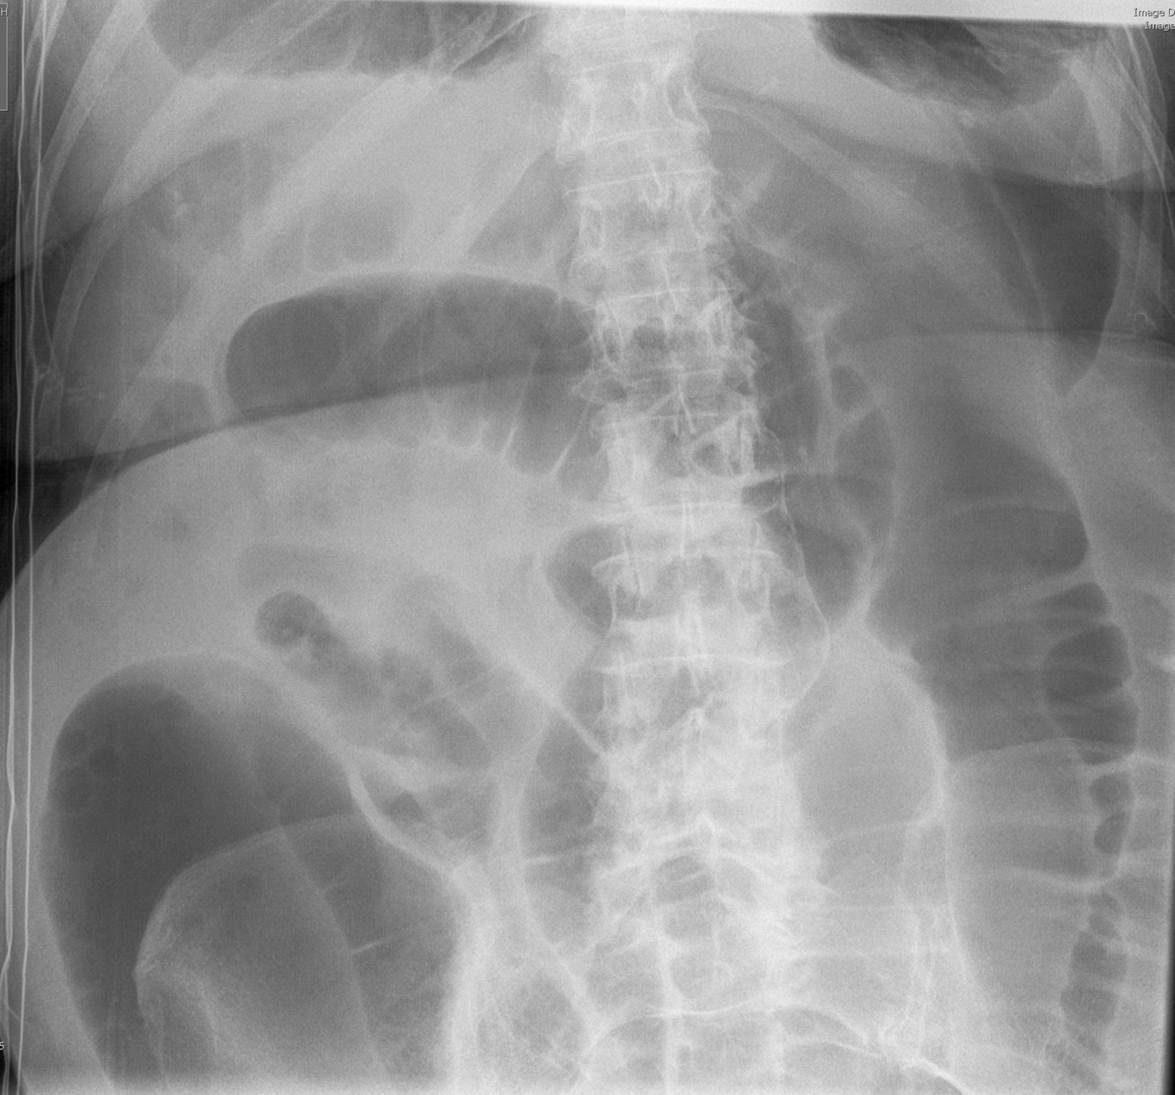

What is the pathology here?

Both SBO and LBO